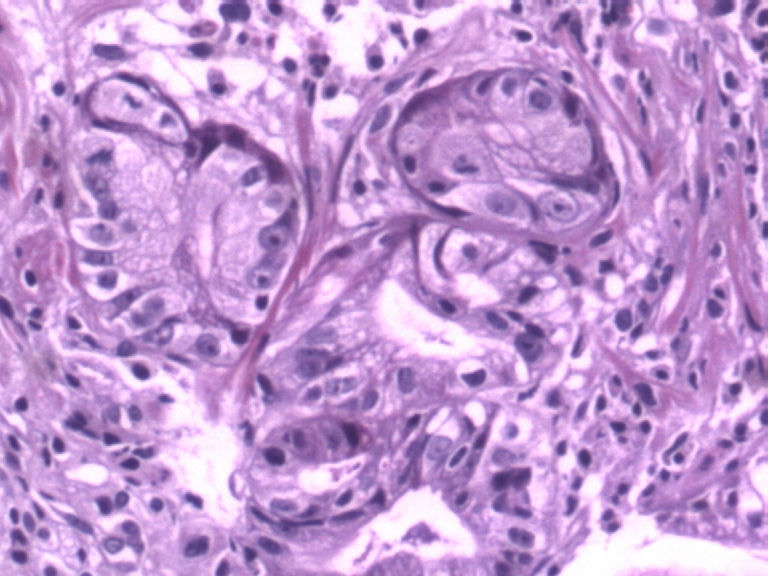

男,50岁,胃镜活检食管下段溃疡组织3块。

• 胃镜活检食管下段溃疡组织3块图4

图4

贲门粘膜炎伴上皮轻度不典型增生。

腺体有不典型增生

腺体有轻度异型,未见粘膜下浸润,应报“低级别上皮内瘤变”。建议重取材或密切随访。

如在食管下段,巴瑞特食管炎要考虑